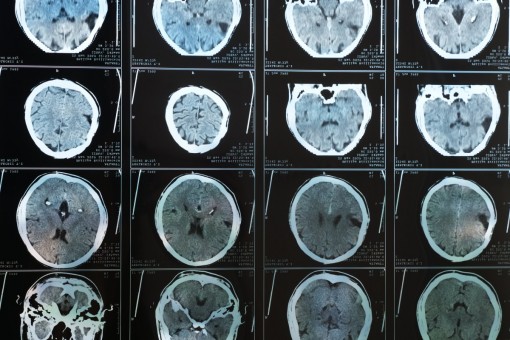

Dữ liệu mới từ một trong những nghiên cứu hình ảnh não lớn nhất thế giới đã phát hiện mối liên hệ giữa việc tăng trọng lượng cơ thể với giảm lưu lượng máu não liên quan đến bệnh Alzheimer.

Theo nghiên cứu mới công bố trên Tạp chí Khoa học Thần kinh, thay đổi khả năng kết nối trong não trẻ có thể là hậu quả của chứng trầm cảm khi mang thai ở người mẹ.